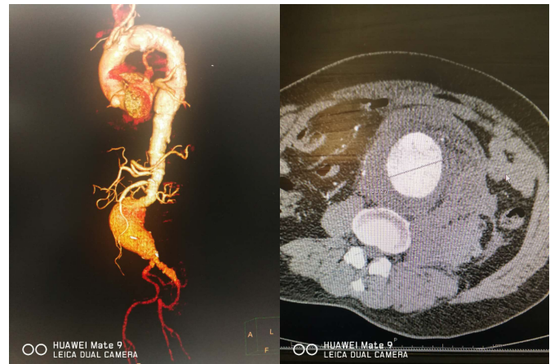

cta显示动脉瘤整体面貌ct断层显示动脉瘤最大直径可达10cm腹主动脉